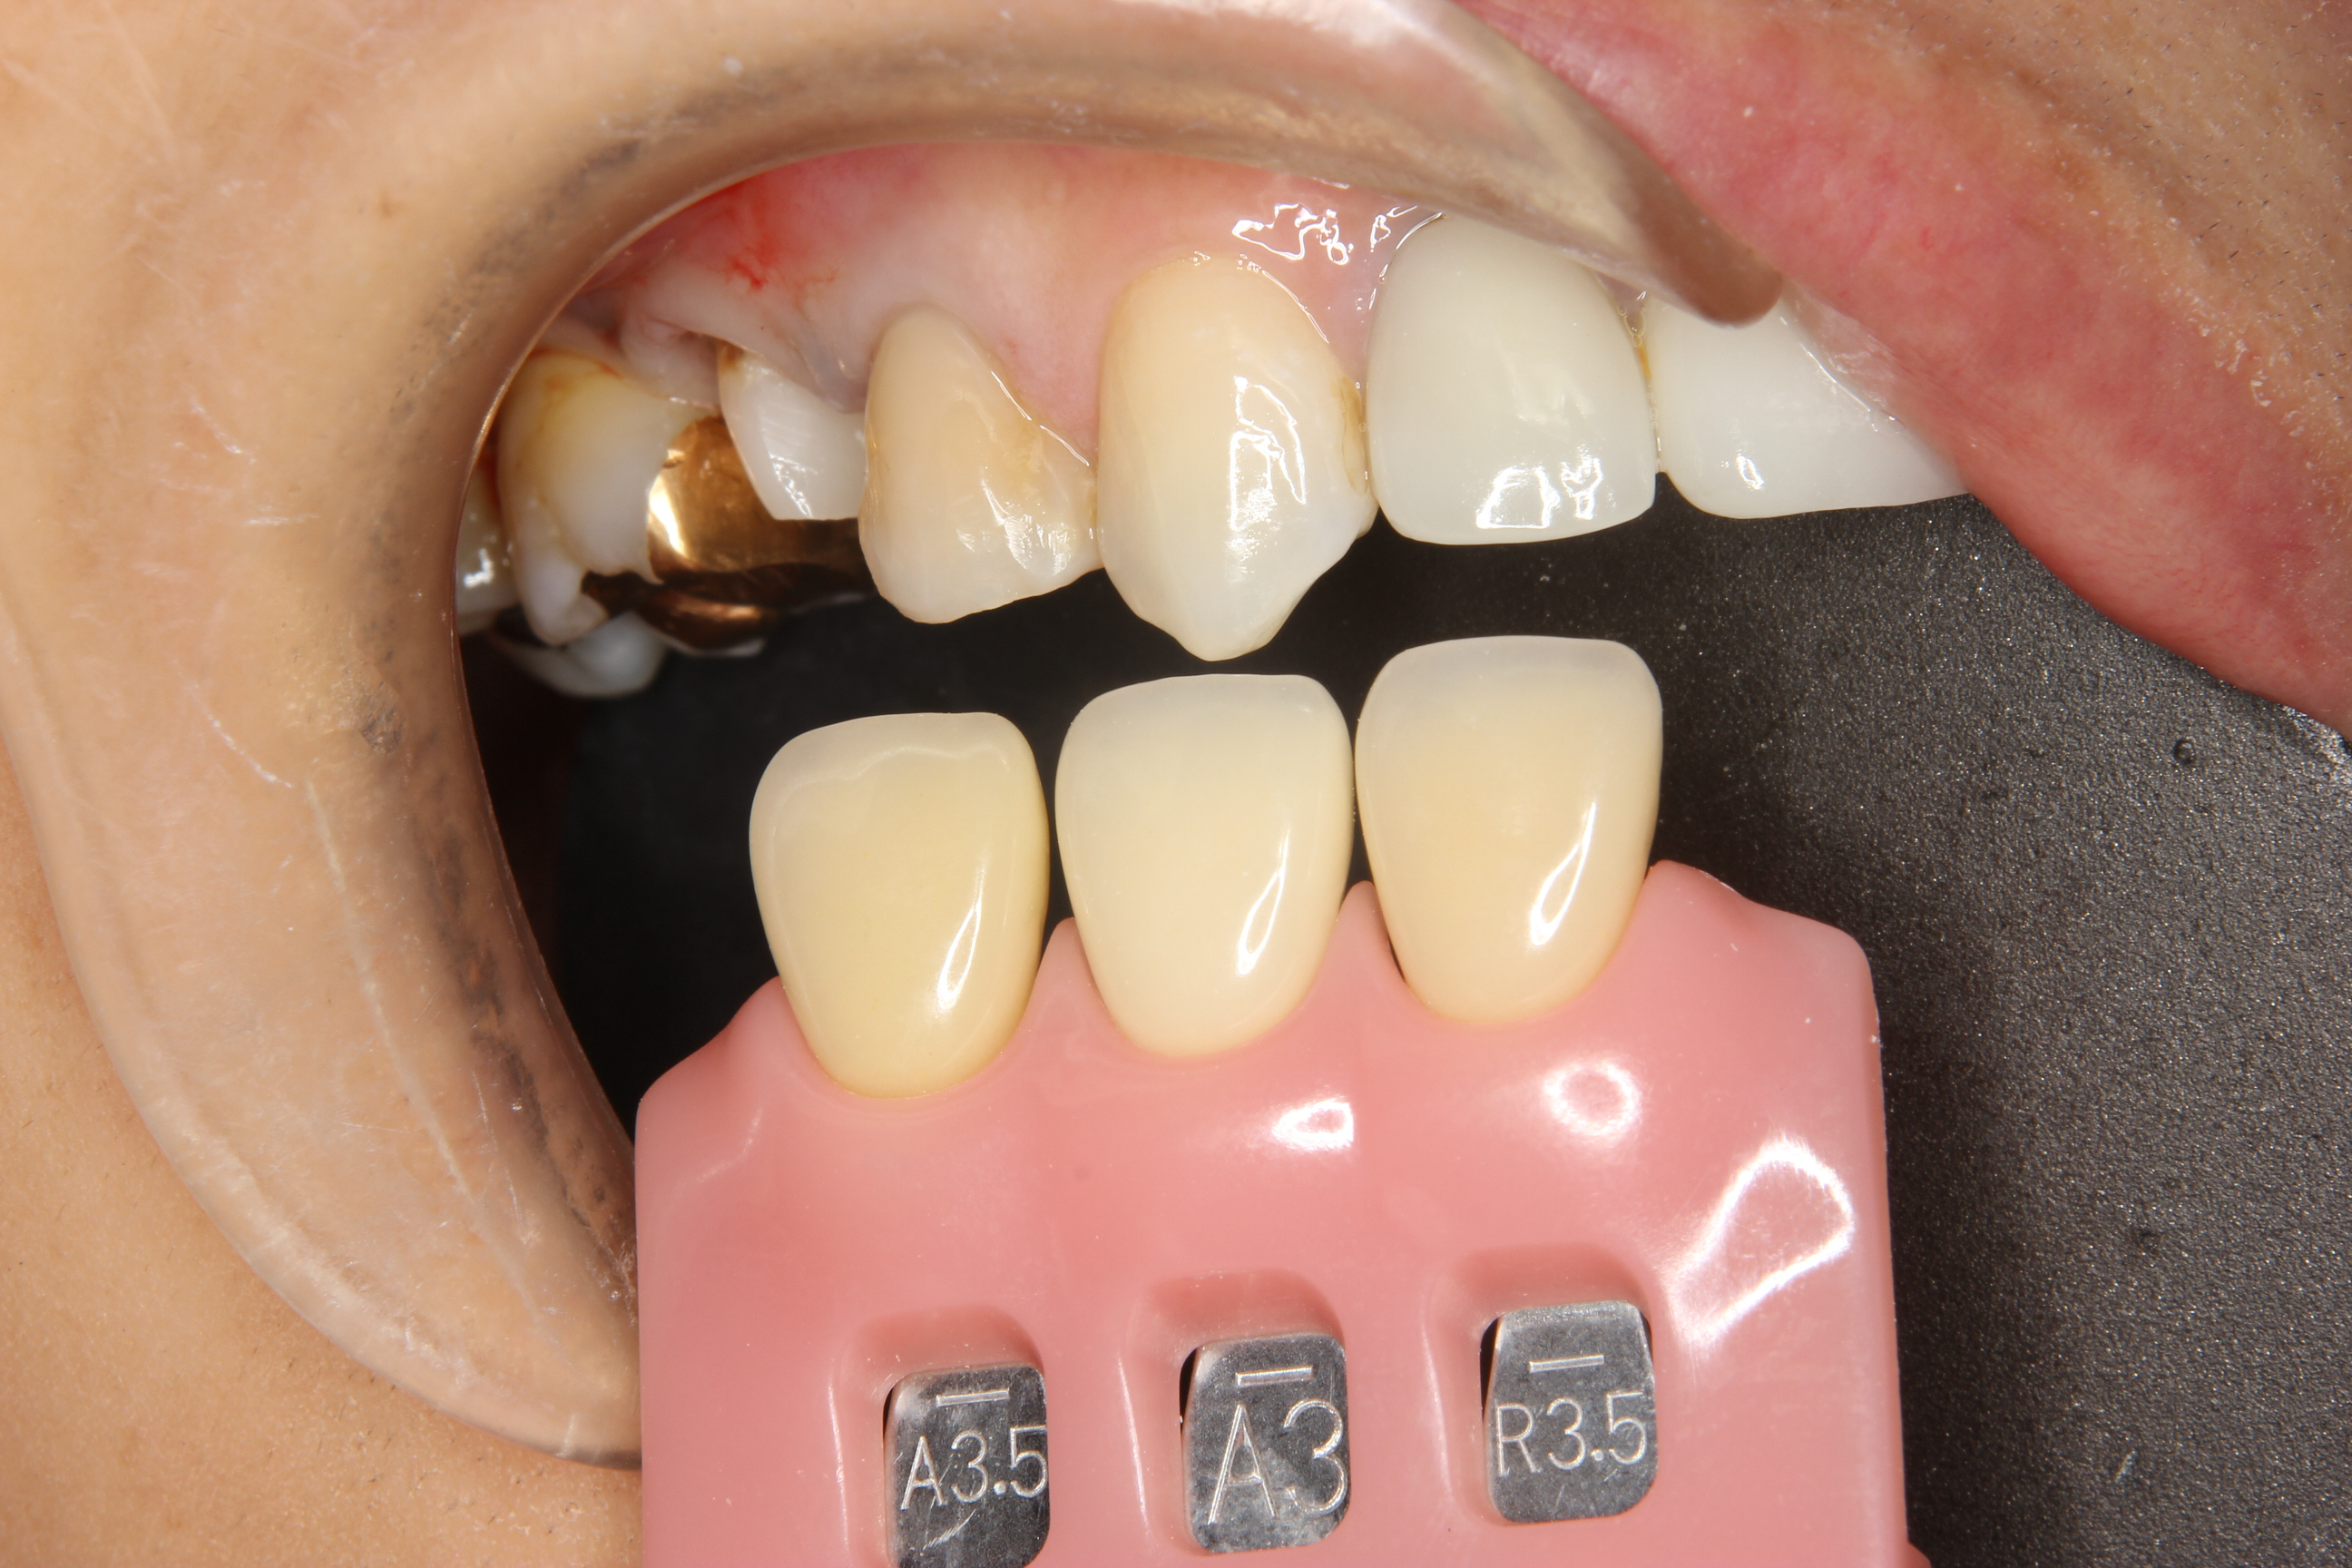

写真は、前歯の被せもの(クラウン)が脱離したということで来院された患者さんです。

クラウンだけでなく、一緒にコア(土台)も脱離している状態でした。

脱離した歯も含めて、4本の前歯にオールセラミックスクラウンが装着されておりました。

根管充填後、土台としてファイバーコアを装着し、オールセラミックスクラウンを作製しました。

作製したクラウンは、以前装着されて残っているクラウンに合わせるように作製し、見た目の違和感がないようにしました。